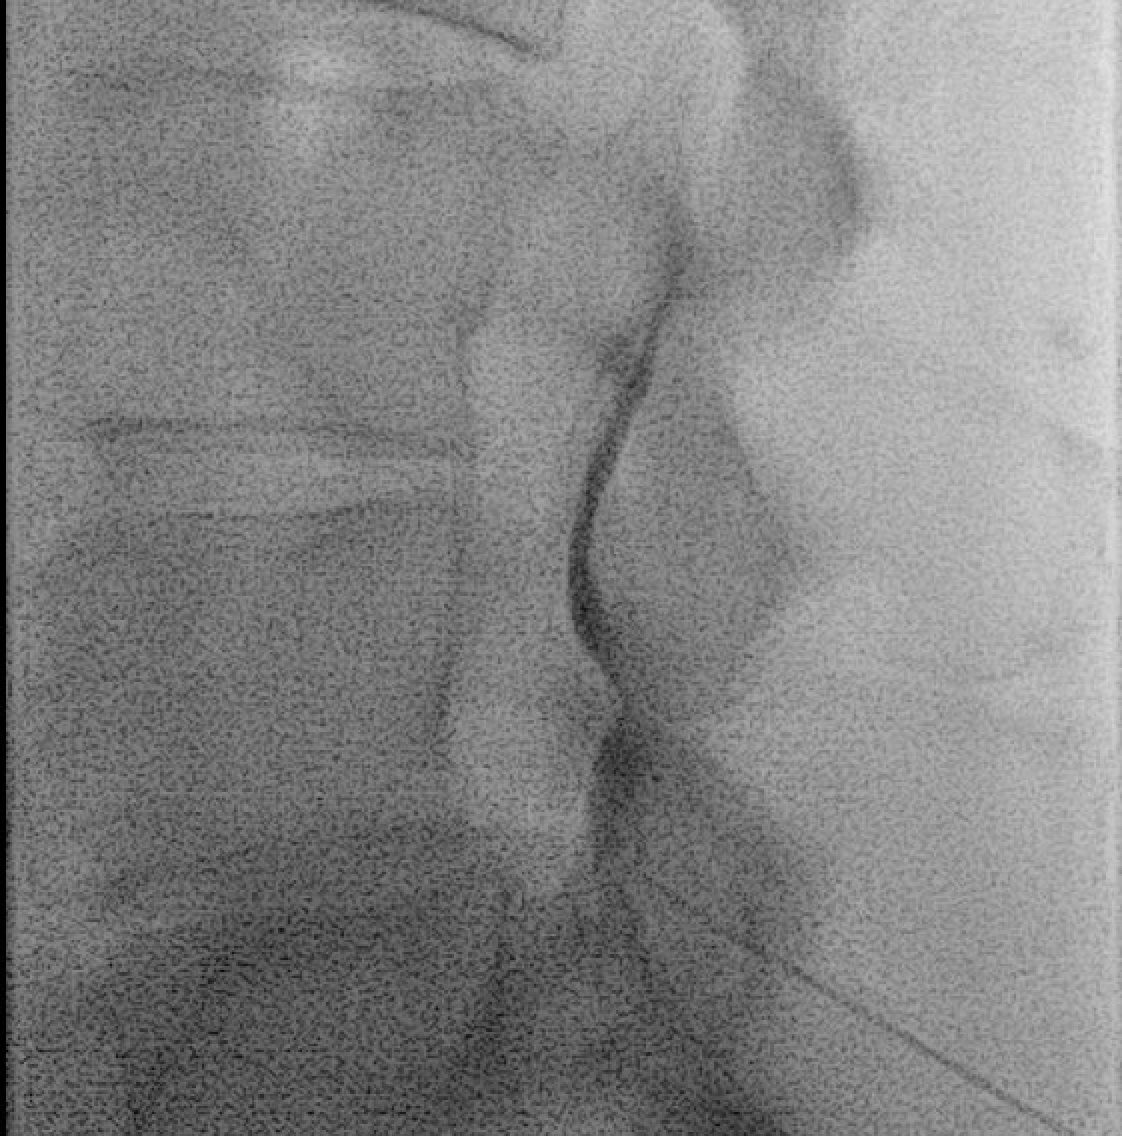

Contrast test dose: 1–2 mL iodinated contrast under live fluoroscopy → expect bilateral epidural spread pattern ("cobweb" or "Christmas tree" shadowing along dural sac and nerve roots).

Interlaminar needle placement under fluoroscopy — paramedian approach through the ligamentum flavum at L4–L5 or L5–S1 interspace.Contrast test showing the characteristic epidural spread pattern — tracking bilaterally around the dural sac and along exiting nerve root sleeves. Confirms correct placement prior to steroid injection.